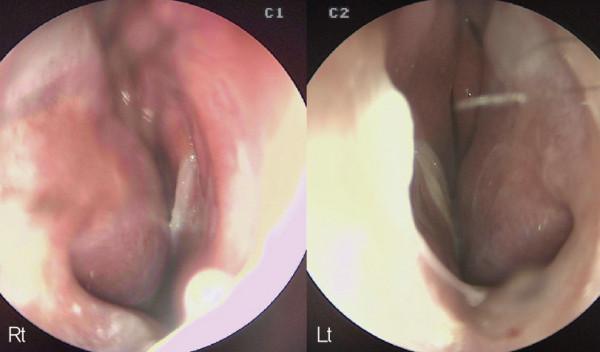

![]()

수술 전 비 내시경. 전체적인 비중격이 우측으로 만곡되어 C-shape deviation을

보인다. 비중격 중간 부분에 천공과 주변으로 만성 염증도 관찰되었다.

내시경 검사상 CT 검사에서보다 심하게 비중격 만곡을 보이고 있었으며, 비밸브 협착도 보여 자가늑연골을 이용한

비중격·천공 재건과 비 성형을 계획하였다.